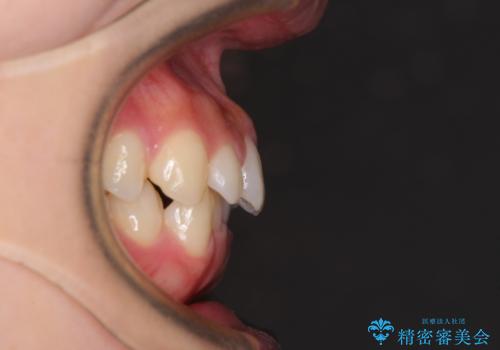

最新の症例

Latest cases